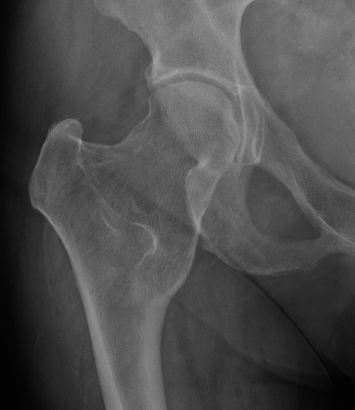

Hip

- coxa valga

- neck short & broad

Mult OC hipHip Osteochondroma

Hip HME

Issues

Coxa valga

Hip subluxation

Guided growth

Hung et al J Paediatr Orthop 2023

- 12 patients with HME and coxa valga / hip subluxation

- guided growth improved neck shaft angles and epiphyseal angles